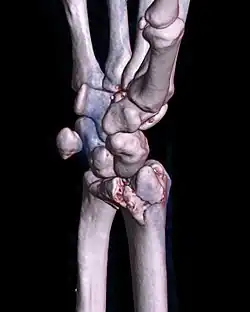

| A palmar Barton's fracture of the right wrist, as shown on a 3D-rendered CT scan | |